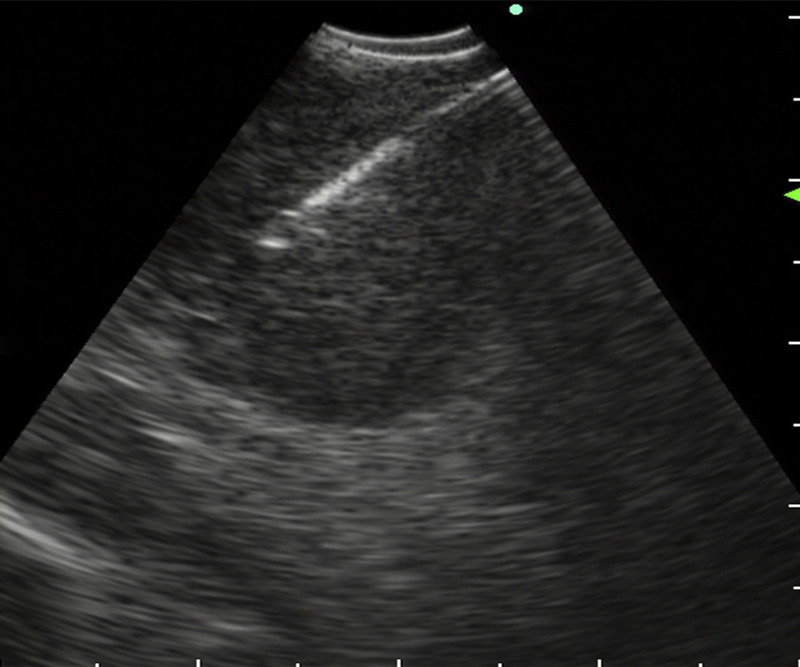

EUS-FNA to diagnose a submucosal oropharyngeal carcinoma.